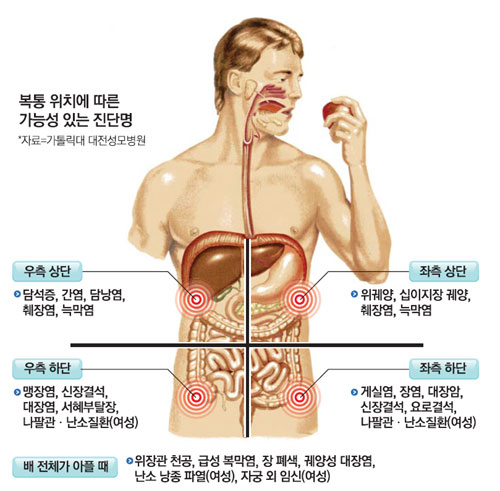

적어도 일주일에 한 번 정도는 염증 치료를 받으러 방문할 수 있지만, 그 과정에서 왼쪽 태반 밑에 남은 통증은 결국 관리가 필요해 비용과 시간 모두 비효율적으로 보였습니다.두통증은 왼쪽 태양과 관절염 등 심근통증으로 인한 근육 통증, 통증, 통증, 통증, 통증, 통증, 통증 등 근육 통증을 유발한다.그래서 저는 결심했습니다.나는 그것을 시도해봤어요.위 아래 통증에 직접 사용한 사용 후기사실, 초기 비용은 조금 높았지만, 제가 계속 사용하고 있다고 가정하는 것보다 훨씬 효율적이었습니다.제가 그것을 받았고, 우리가 예상했던 것보다 더 빨리 고통받는 지역보다 빨리 보살핌을 받았습니다.배가 위쪽에 있는 배가 아파요. 배가 위쪽에 통증을 호소했지만, 위쪽에 있는 근육에 통증이 심해졌다.나는 솔직히 즉각 반응을 보였다.사실 초기 비용은 조금 비쌌지만, 계속 사용한다고 가정하면 직접 가지러 가는 것보다 효율적이었습니다.제가 받아서 사용했는데, 생각보다 아픈 부위를 빨리 치료해 주었습니다.위의 오른쪽 구덩이의 통증 > 왼쪽 구덩이의 통증 > 위의 구덩이 아래의 통증 순서대로 아팠지만, 위의 구덩이 주위를 모두 사용한 후에는 안쪽에서 근육이 당기는 느낌이 사라졌습니다.저는 솔직히 즉각적인 반응에 놀랐습니다.이 방법은 오래전부터 전류를 통한 통증 관리의 일환으로 여러 기관에서 널리 사용되고 있어 집에서도 안심하고 사용하실 수 있습니다!한국에서 개발된 리무버인 줄 알았는데 아니었어요.유럽인들이 갑자기 고통을 준비하기 때문에 디럭스 스토리를 준비하기 어렵다.오른쪽 피치 통증을 위해 사용하면서 근육은 근육이 약간 느슨하게 느껴졌고, 근육이 약간 느슨하게 느껴졌다.전기가 있으면 안 아파요. 하지만 오른쪽 시원한 느낌은 기분이 좋을 것 같아요.높은 휴대성과 편리함으로 사용하기 좋습니다또 다른 장점은 일상 생활에서 운반할 수 있다는 것입니다.갑자기, 통증이 심해지고 숨을 쉴 때, 특히 숨을 들이고 숨을 쉴 때렸다.그리고 무의식적으로 이 자세를 취해서 고통을 느꼈을 때 내 일에 집중하기 힘들었다.하지만, 통증이 갑자기 올라가면, 내 옷을 벗기고, 옷 위에 올려서 호흡이 더 빨리 통증이 심해지고, 진통제가 더 빨리 치료하기가 더 빨라졌다.일상생활에서 휴대할 수 있고 원할 때 언제든지 사용할 수 있다는 점도 장점으로 꼽혔습니다.특히 몸을 뒤로 젖히거나 숨을 크게 쉴 때 갑자기 따끔거리고 통증이 느껴졌습니다.그리고 무의식적으로 이런 자세를 취하며 고통을 느낄 때, 잠시 지속되었기 때문에 일에 집중하기가 어려웠습니다.하지만 지금은 갑자기 통증이 높아지면 기기를 꺼내 옷에 붙이고 클릭하면 숨막히는 통증이 금방 진정되기 때문에 진통제를 먹는 것보다 훨씬 빨리 치료하는 것이 좋았습니다.오른쪽 태음순의 통증과 태음순 아래의 통증 외에도, 여러분은 피부와 근육이 위치한 곳이라면 어디서든 사용할 수 있습니다!저는 기계의 지원을 받아 그것을 썼습니다.